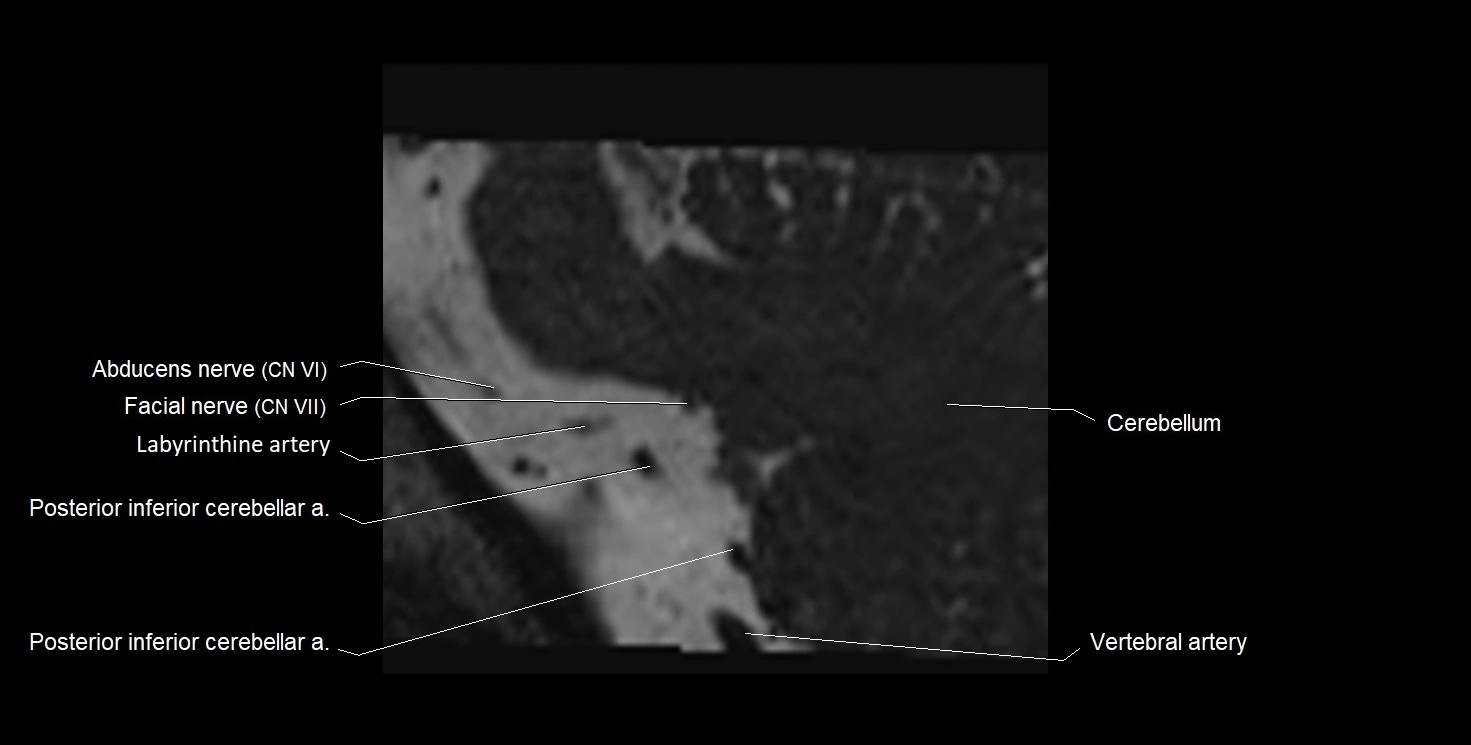

MRI Appearance

• The abducens nerve is a small, thin, linear structure

• Best visualized on high-resolution T2-weighted 3D MRI sequences (e.g., FIESTA or CISS)

• Seen as a hypointense (dark) line running from the brainstem at the pontomedullary junction, traversing the prepontine cistern, and entering Dorello’s canal under the petrosphenoidal ligament, then into the cavernous sinus, and finally the orbit

• May be challenging to visualize in standard MRI due to its small size

• Pathology may be inferred by absence, displacement, or enhancement of the nerve